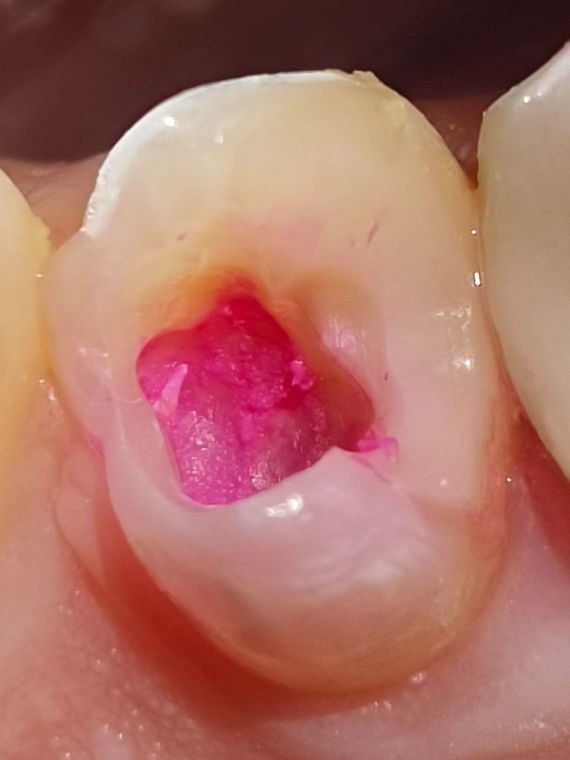

окрашивание

Окрашивание специальным индикатором "Кариес-индикатор" показывает зоны поражаения ярко малиновым цветом. Такие ткани необходимо убирать.

Мягкий дентин

Так же на фото можно увидить "комочки" тканей мягкой консистенции - это CID дентин. То есть ткани инфицированные кариесом.